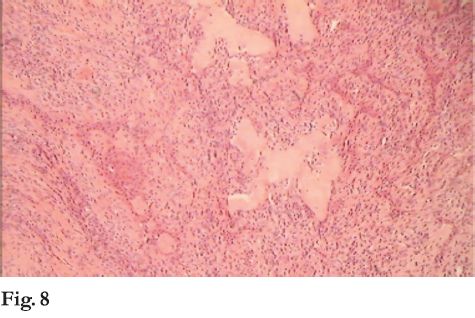

Diagnóstico clínico presuntivo: lesión hiperplásica reactiva. Se realiza biopsia incisional. Histopatológicamente debajo de mucosa pavimentosa crece una proliferación esencialmente fibromatosa caracterizada por presentar epitelio odontogénico en forma de largos cordones anastomosados entre si, adyacentes a material hialino, globular, con calcificación focal (fig. 8 y 9).

El diagnóstico histopatológico fue de tumor odontogénico periférico con los caracteres de un fibroma odontogénico con “glóbulos hialinos”.